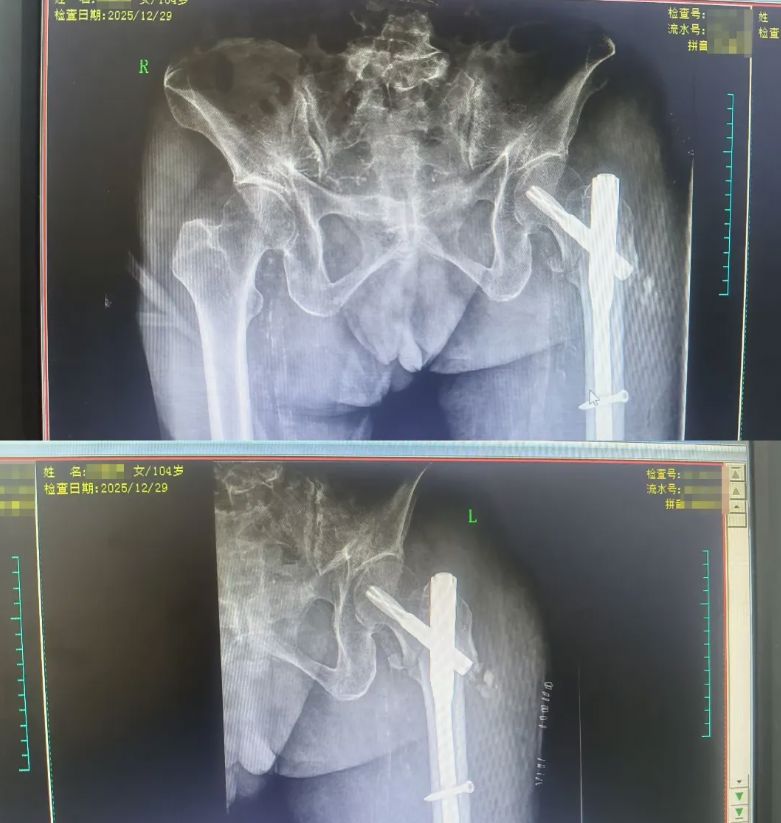

经过骨外科二区李玉春主任医师和黄国聪副主任医师的全面评估,与家属充分沟通后,决定为患者实施微创经皮复位PFNA术。团队组织疑难危重病例讨论,制定个性化治疗方案,克服了高龄患者麻醉难度大、手术风险高等重重困难。

术后,护理团队通过个性化康复指导与心理疏导,指导陈阿姨早期进行踝泵训练、肌肉收缩等功能锻炼,配合抗骨质疏松治疗,帮助她克服因疼痛恐惧而拒绝锻炼的心理障碍,实现“无血、无惧、无痛、无栓”的快速康复。陈亚姨身体状态恢复良好,目前已能在无负重下活动,顺利出院。